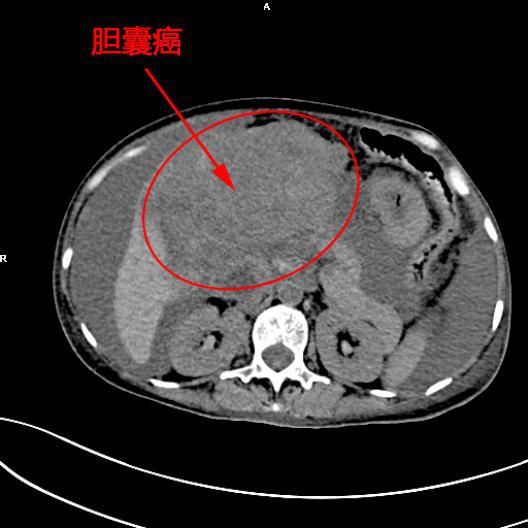

患者陳女士,57歲,汕頭潮南人,2個月前出現右上腹痛,在汕頭大型三甲醫院确診爲膽囊癌,因腫瘤爲晚期,已擴散至肝髒、十二指腸,患者放棄在汕頭治療,回家後自行采用中藥治療。近期右上腹痛加重,反複排黑便,遂來我院住院,診斷爲膽囊癌伴活動性出血。

5月11日下午,内三科主任李旭丹、影像科副主任胡志華上台施術。通過粵東領先的飛利浦DSA造影顯示,患者腫瘤供血血管豐富,膽囊動脈造影可見腫瘤染色明顯,有造影劑外溢,提示部分血管末梢有破裂出血現象,探查胃十二指腸動脈及腸系膜上動脈未見出血征像,豐富的血供使腫瘤能獲取大量的營養快速生長,血管末梢的破裂出血導緻患者反複黑便。